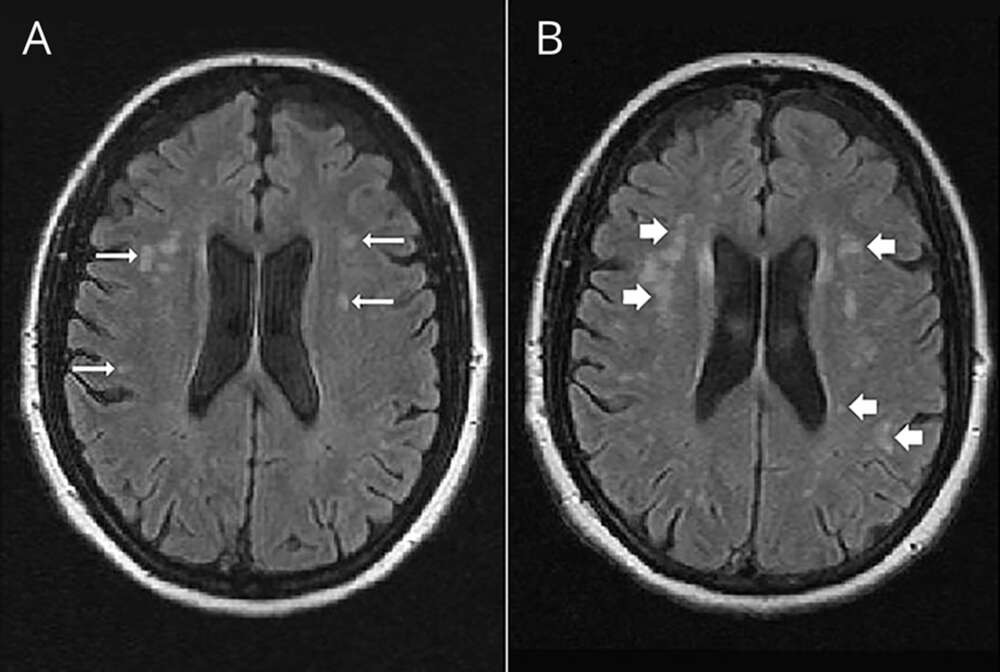

چه زمانی لازم است PFO بسته شود؟

آیا لازم است تمام افراد با PFO آن را درمان کنند؟

عوارض و خطرات PFO

PFO چه علایم و چه خطراتی می تواند داشته باشد؟